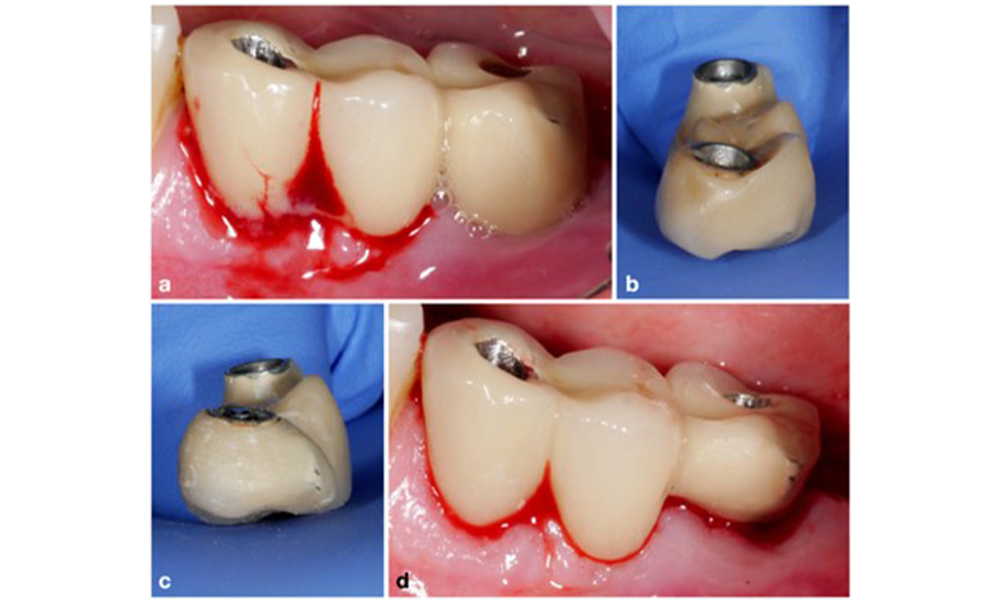

Auf dem World Workshop on the Classification of Periodontal and Peri‐Implant Diseases and Conditions 2017 wurden diagnostische Kriterien für periimplantäre Mukositis und Periimplantitis festgelegt (Renvert et al. 2018). Periimplantäre Mukositis ist definiert als (1) Entzündung um das Implantat (also Rötungen, Schwellungen, Blutfäden oder Blutstropfen innerhalb von 30 Sekunden nach dem Sondieren), jedoch (2) ohne zusätzlichen Knochenverlust nach der Ersteinheilung (Abb. 1).

Implantat an Position 26 mit periimplantärer Mukositis (a-c). Die Sondierungstiefe von 5 mm (b) stimmt mit der wenige Wochen nach dem Einsetzen der prothetischen Rekonstruktion vorgenommenen Messung überein. Es kommt zwar zu einer Sondierungsblutung (c), aber die Röntgenaufnahme zeigt keinen weiteren Knochenverlust über das Maß hinaus, das bei einer marginalen Knochen-Remodellierung zu erwarten ist (d).

Abb. 1. Implantat an Position 26 mit periimplantärer Mukositis (a-c). Die Sondierungstiefe von 5 mm (b) stimmt mit der wenige Wochen nach dem Einsetzen der prothetischen Rekonstruktion vorgenommenen Messung überein. Es kommt zwar zu einer Sondierungsblutung (c), aber die Röntgenaufnahme zeigt keinen weiteren Knochenverlust über das Maß hinaus, das bei einer marginalen Knochen-Remodellierung zu erwarten ist (d).